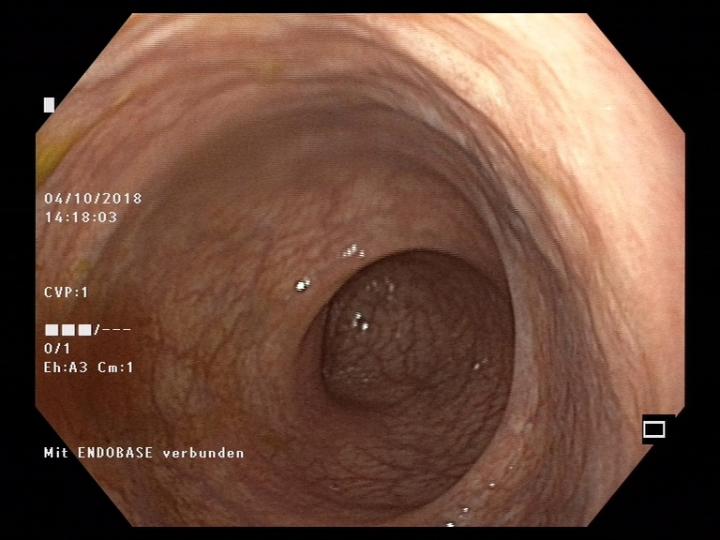

There are different forms of inflammatory bowel disease (IBD) - Crohn's disease (which affects different segments of the entire intestinal tract) and ulcerative colitis (which affects the large intestine). These conditions affect about 30 people per 100,000 of the European and North American populations. Over the last 10 years the incidence of IBD in Switzerland has sharply increased: in 2004 there were about 12,000 patients compared with 20,000 in 2014. Since IBD usually starts before the age of 35, with major ongoing limitations for the quality of life and ability to work, the conditions also have severe social and economic consequences.

New results have now been reported on the relationships of intestinal bacteria in IBD patients by the research team led by Andrew Macpherson, Bahtiyar Yilmaz und Pascal Juillerat in the Department of Biomedical Research in the University of Bern and the University Clinic of Visceral Surgery and Medicine of the Inselspital. They have discovered that changes of particular species of intestinal bacteria lead to severe relapsing disease resistant to therapy and even make the return of the disease more likely in patients whose active segments of Crohn's disease have been surgically removed. The work is being published in the journal Nature Medicine .